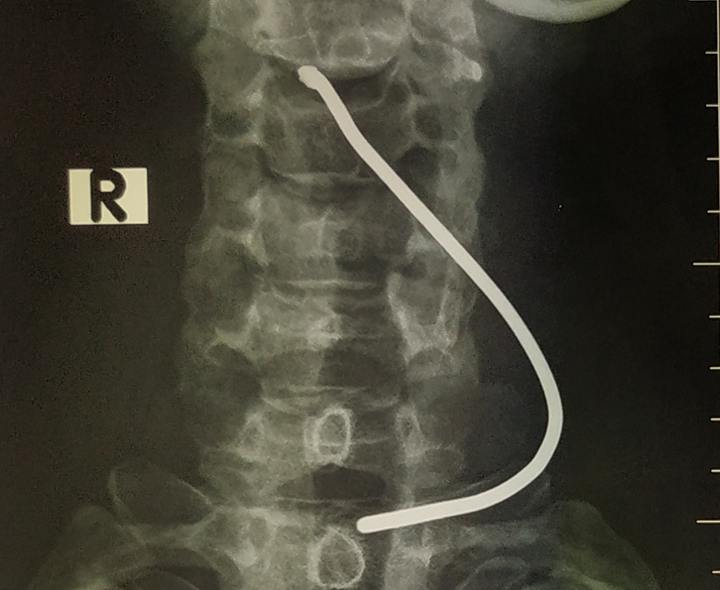

Hình ảnh phim chụp thanh sắt đâm vào cổ bệnh nhân.

Bệnh nhân nhập viện với tình trạng sức khỏe tỉnh táo, vùng cổ có vết thương thanh quản 0,5cm do dị vật là thanh sắt bắn vào đã gây tổn thương sụn giáp.

ThS.BS Dương Ngọc Thắng - Trung tâm Tim mạch và Lồng ngực, Bệnh viện Hữu nghị Việt Đức thực hiện phẫu thuật thăm dò vết thương cho bệnh nhân, lấy dị vật, khâu vết thương sụn giáp. May mắn thanh sắt xuyên qua sụn giáp, đi vào thanh quản nhưng không tổn thương dây thanh âm.